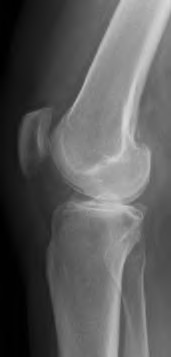

A 67 year-old woman sustained an ACL tear while playing basketball when she was 35 years-old. She has noted progressive leg deformity and episodes of giving way, and now has pain preventing activity. Non-operative management has failed to provide relief. Treatment should consist of?

The radiograph seen in Figure A reveals varus alignment of the knee, with medial tibial deficiency; from this X-ray the patient appears to have unicompartmental arthritis. Treatment options for unicompartmental arthritis include high tibial osteotomy, interpositional arthroplasty, unicondylar knee replacement and total knee replacement. Interpositional arthroplasty became popular in the 1950’s when early outcomes analysis seemed to indicate good results; long term follow up in one study found 0/12 excellent results, with all patients requiring conversion to TKA. This procedure is no longer recommended due to the poor long term outcomes.

While an osteotomy is still used for young and active patients, unicompartmental or total knee arthroplasty have largely replaced this treatment in older patients. Advantages of UKA and TKA include more predictable relief of pain, quicker recovery, and better long-term results. Criteria for UKA include limited unicompartmental disease, no more than a fixed 10 degrees of varus or 5 degrees of valgus deformity from neutral and an intact anterior cruciate ligament with no signs of medial lateral subluxation of the femur on the tibia; this patient is therefore not a good candidate for this procedure.

Total knee arthroplasty can be used to provide predictable pain relief in a patient with unicompartmental and tricompartmental degenerative disease and varus malformation of the knee and for this patient is the best option.